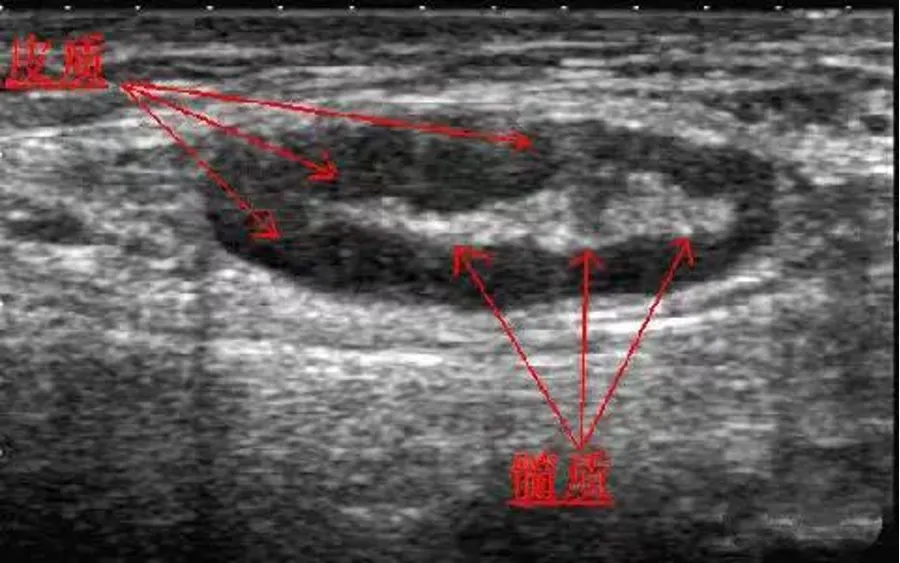

● 形态:呈偏长椭圆形,包膜清晰,表面光滑

● 大小:大多数长径(L)<20mm,少数也可以超过30mm,厚径(S)<6.5mm,L/S≥2。单一的长径无临床使用价值。

● 内部回声:周边皮质呈均匀低回声,中央髓质呈窄条状高回声。淋巴结门位居中或者稍偏一侧。有时门位显示不清。

● CDFI检查:门位血流,动脉经淋巴门从髓质向皮质区呈放射状、树杈状、或仅显示髓质内点状或条状血流信号。

脉冲多普勒检测淋巴结内动脉血流为低速低阻型(0.57±0.1)。